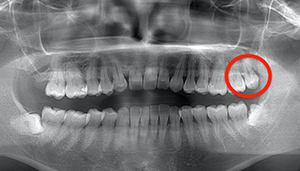

左下の歯茎が腫れている親知らずの症例

- 抜歯前写真(レントゲン、CT等)

左下の親知らず周囲歯肉が腫れていました。

また、手前の歯との間で虫歯もできていました。

3分割して抜歯しました。

| 年齢 | 20代・女性 |

|---|---|

| 主訴 | 左下の歯茎が腫れている |

| 適応するプラン | スタンダード親知らず抜歯プラン |

| 親知らずの生え方 | 歯茎から少し頭が出ている |

| 抜歯時間 | 15分 |

| 費用 | 約7,000円 |

| 抜歯内容 | 下顎の親知らずの抜歯希望の患者様です。 智歯周囲炎となっており、初診時では麻酔が効きづらい旨をお話しし、初診時は抗生物質をお出ししました。1週間後、ある程度歯肉の炎症がとれたことを確認して抜歯を行いました。 麻酔を行い、遠心(親知らずの奥側)歯肉と、手前の歯の頬側の歯肉を切開しました。 歯茎を開いて、手前の歯と引っかかっている部分をカットしました。 その後、骨からでている歯冠部(頭の部分)をカットしました。 その後へーベルで歯根(骨に埋まっている部分)を脱臼し、抜歯を終えました。 切開した歯茎を3針縫って、治療終了となりました。 歯茎を切ったため、3日ほど腫れぼったい感じがあったようですが、痛みはほとんどなく、治癒に向かいました。 |